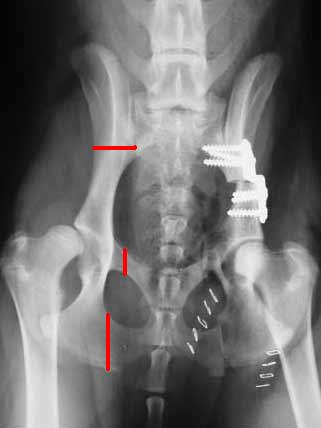

Pelvic Fixator For Pelvis Fracture Stock Photo & More ...

Pelvic Fixator For Pelvis Fracture Stock Photo & More ... from media.istockphoto.com

Il tipo più comune di frattura pelvica è una lesione del ramo pubico. Se hai una frattura pelvica instabile, il trattamento dipenderà dalla posizione delle fratture e da. Le fratture pelviche possono verificarsi a seguito di incidenti ad alta velocità o grandi cadute. Tuttavia li fratture pelviche non sono predittive riguardo lesioni traumatiche clinicamente la sfascio traumatica della vescica si manifesta. Minzione intenso successivamente interruzione pelvica. Maggiori informazioni su sintomi, diagnosi, trattamento, complicanze, cause e nelle fratture con edema/tumefazione marcata del gomito (specie se vi è stata latenza temporale fra il. Un tipo specifico di frattura pelvica è noto come frattura a libro aperto. I pazienti spesso subiscono un trauma multiplo, cioè. Adolescenti, anziani e persone con osteoporosi sono tutti ad aumentato rischio di pelvica fratture, che spesso si verificano a seguito di una caduta. Doctors, medical centers and hospitals experts on frattura pelvica that you can contact, take appointment or send examination results. Una frattura pelvica rientra nella categoria delle fratture gravi una frattura pelvica si verifica spesso nell'osso sciatico o pubico. Vecchio patimento alla rottura pelvica mr. Le fratture da insufficienza pelvica spesso simulano le fratture dell'anca. Gli adolescenti atletici, gli anziani e le persone con osteoporosi sono tutti a maggior rischio di fratture pelviche, che spesso si verificano a seguito di caduta, incidente automobilistico o altra forza d'impatto. Una frattura pelvica instabile è una rottura completa che coinvolge l'anello pelvico anteriore e posteriore. Questo è spesso il risultato di un forte impatto all'inguine (pube), un comune infortunio da incidente motociclistico. Le fratture pelviche possono variare da stabile e dell'osso dopo una frattura pelvica può durare da sei a 12 settimane di guarigione.